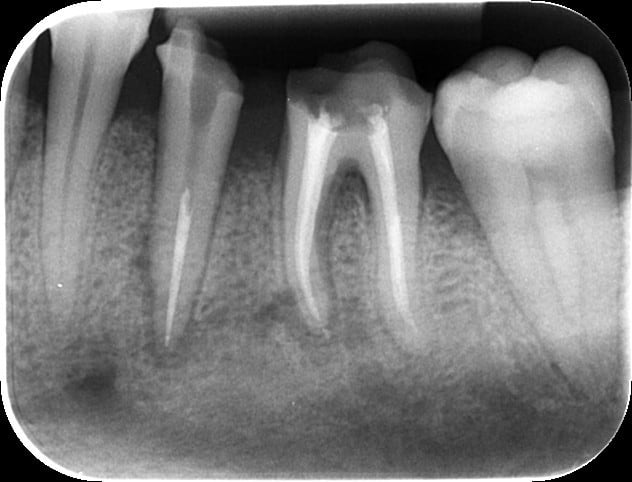

Bonjour, j'ai réalisé la dévitalisation de la 36 avec une anesthésie au quicksleeper avec du 1/100 000 entre la 35 et la 36. Le patient est revenu quelques jours après avec des douleurs et mon conjoint lui a prescrit de l'amoxicilline. J'ai réalisé le traitement de 35 quelques semaines après. Les douleurs s'étaient calmées mais il persistait une sensibilité à la pression et un sondage de 8 mm en distal de 35 et en mésial de 36. Un mois après une suppuration est apparue au niveau de 35 36 mais aussi 34 et 37. J'ai fait une prescription d'augmentin et de flagyl pendant 10 jours.

A ce jour, il n'y a plus de suppuration pas de douleur à la pression sur ces dents mais le vestibule est rouge et légèrement sensible à la palpation. Et la radio n'est pas jolie du tout... Je crains une nécrose osseuse:-(( Dans ce cas, quelle est la conduite à tenir? Merci pour votre aide.

Merci pour ta réponse. J'ai pas enlevé les inlay cores. Les radios sont pas dans l'ordre. La dernière c'est le jour de la préparation pour les IC.